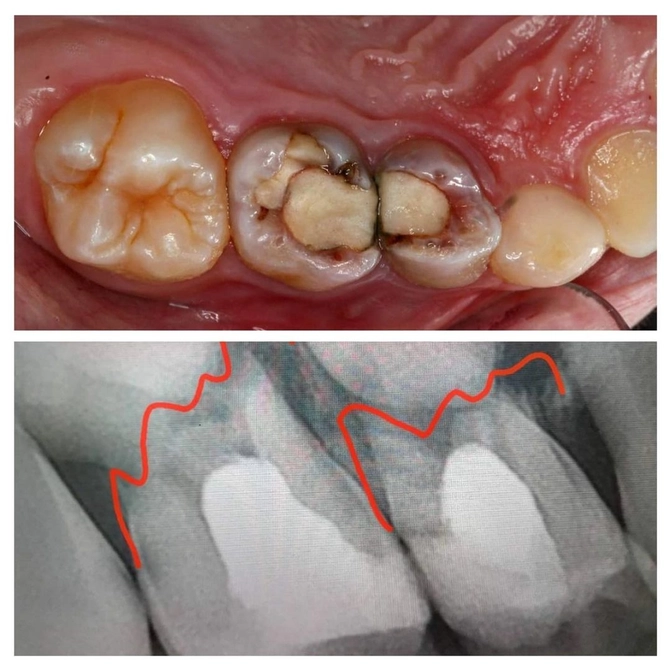

На снимке видим, что корни обоих зубов уже рассосались, а воспалительный процесс под ними угрожает зачаткам постоянных зубов.

"Четверка" и "пятерка" были слабо подвижны и держались в челюсти из-за уплотнения связок, которое возникло после лечения резорцин-формалиновым методом.

✔️Оба зуба удалены.

✔️На контакте между удаленной "пятеркой" и "шестеркой" видим кариозный процесс.